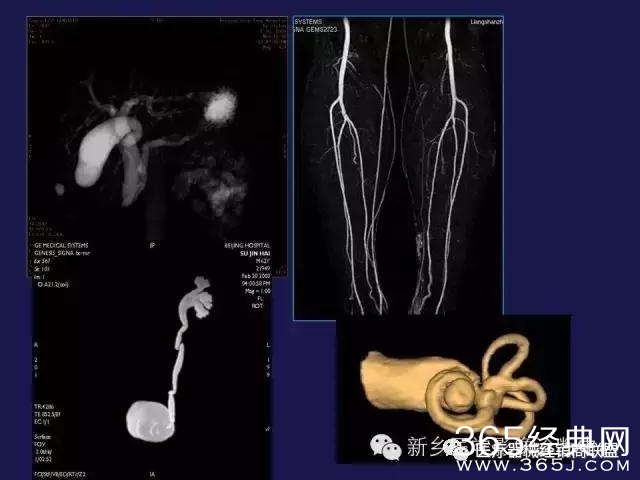

CT、MRI很难?NO,今日我们一起来学习一下如何读CT、MRI!

内行看门道:

整整90张图